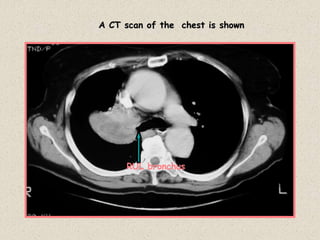

Case 25

A CT scan of the chest is shown

RUL bronchus

Diagnosis: Right Upper lobe collapse due to an

endobronchial carcinioma